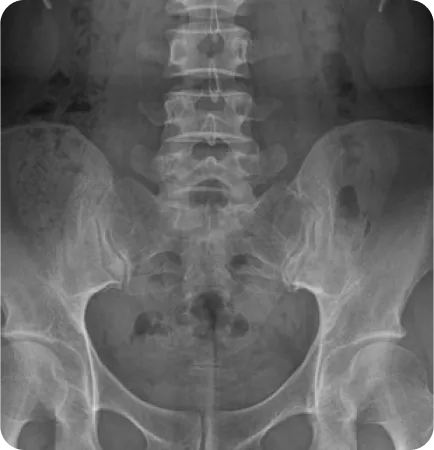

Before & After

해당 사진은 수정없는 실제 치료사진입니다.

환자의 치료결과는 환자의 상태, 치료방법 등에 따라 차이가 발생할 수 있습니다.